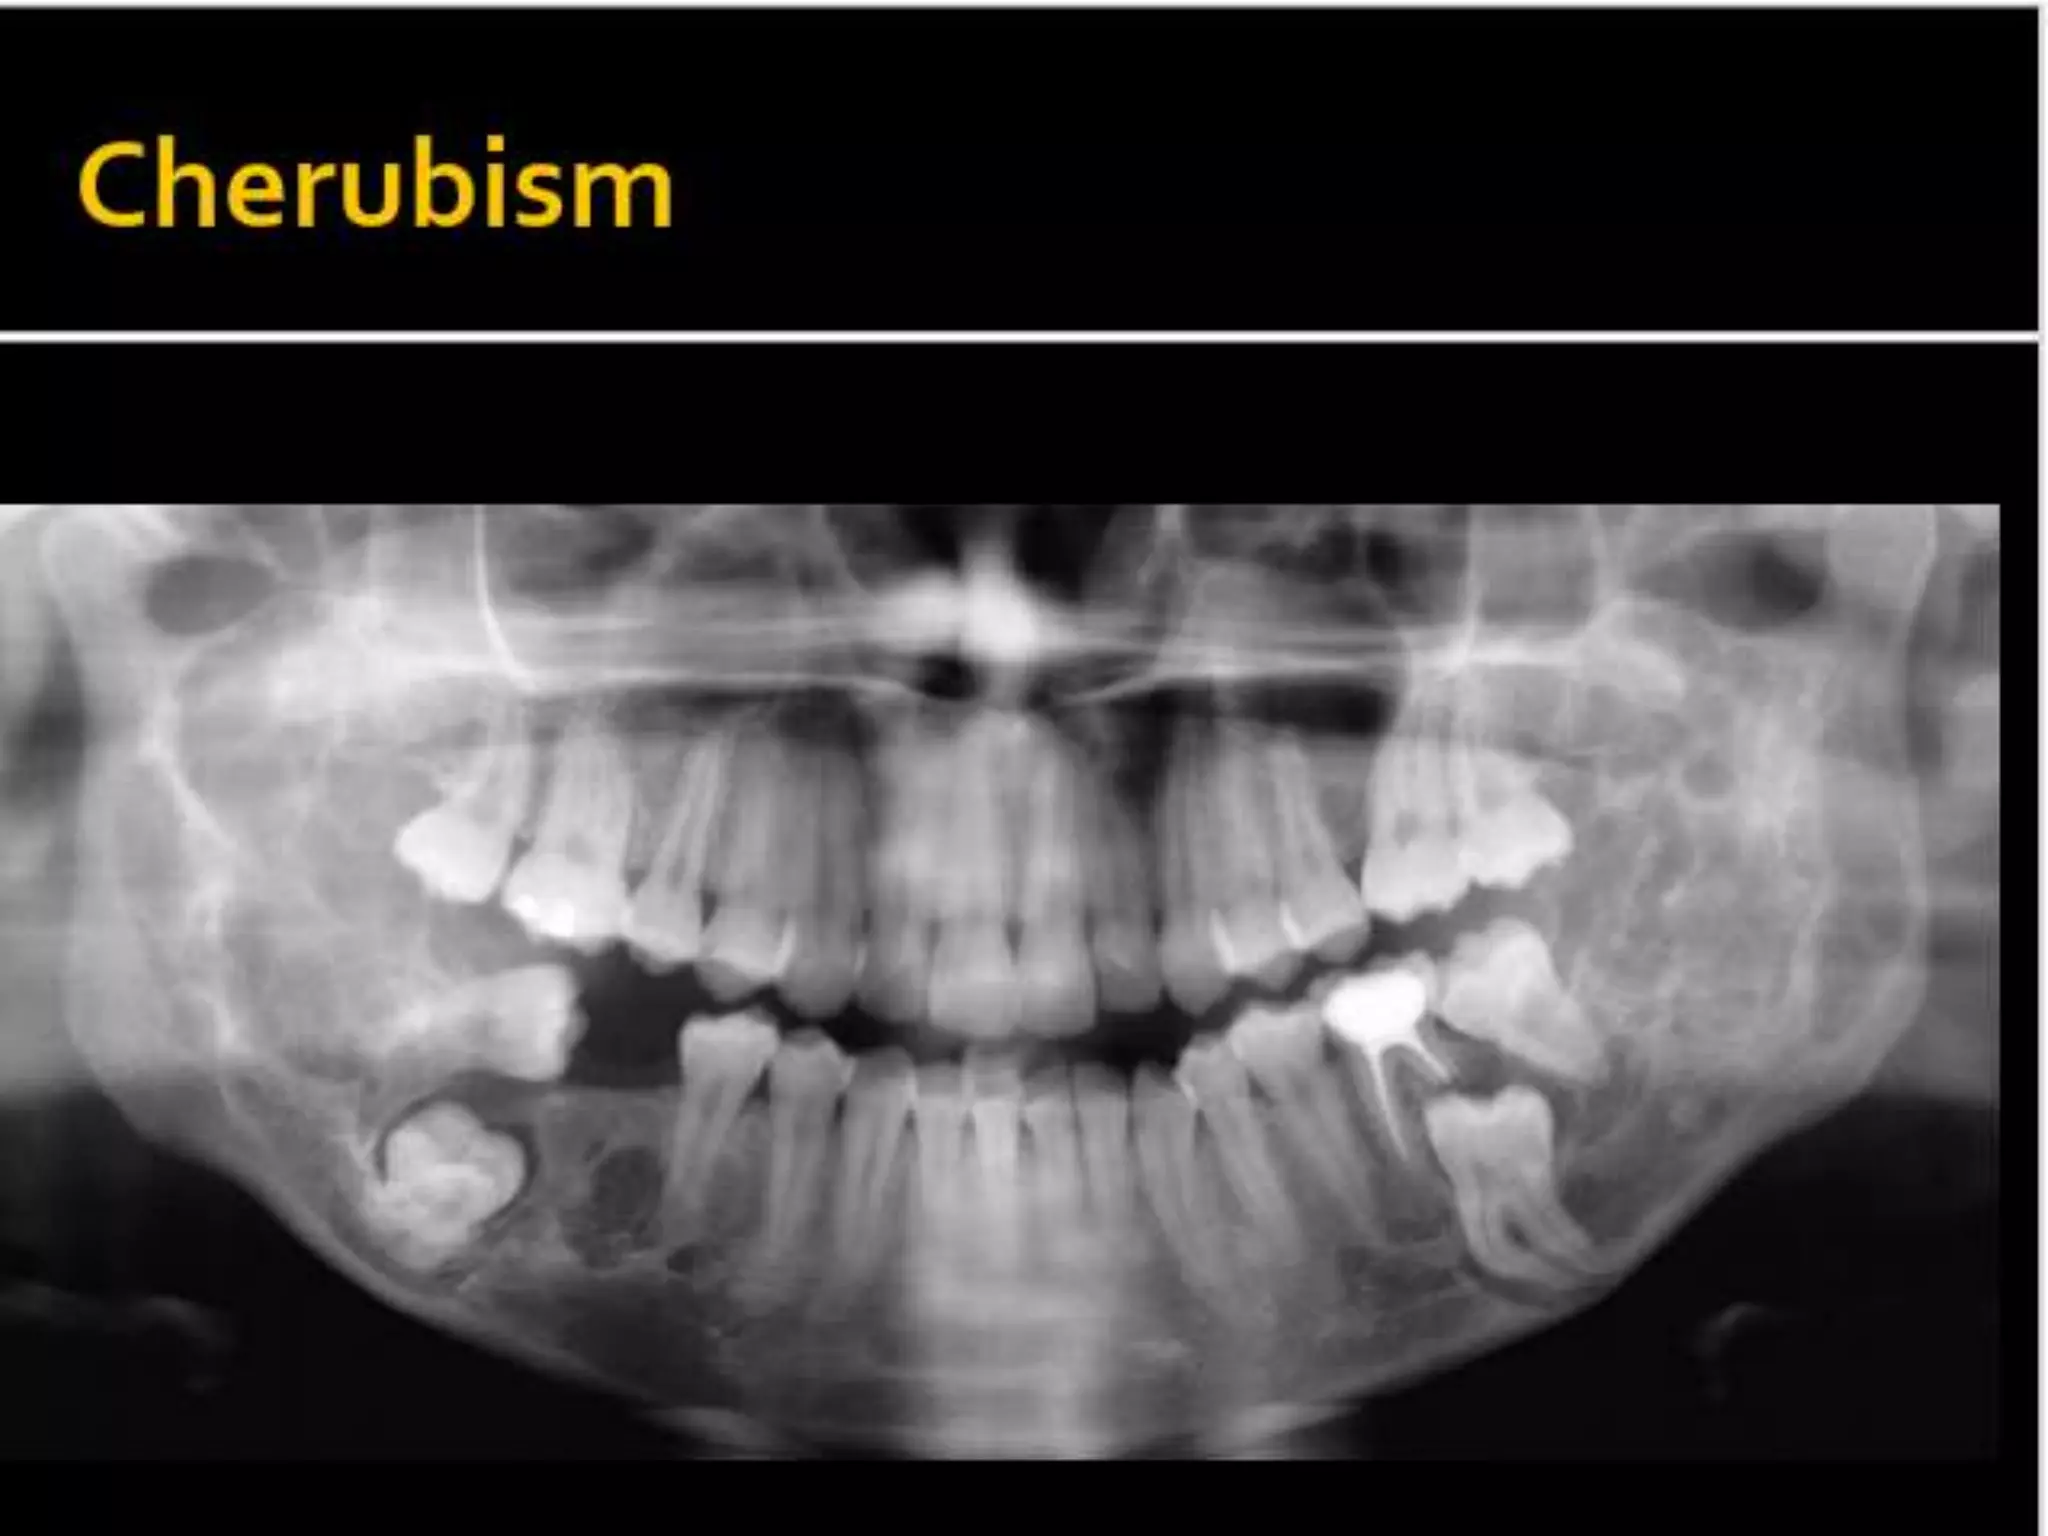

MPS VI.